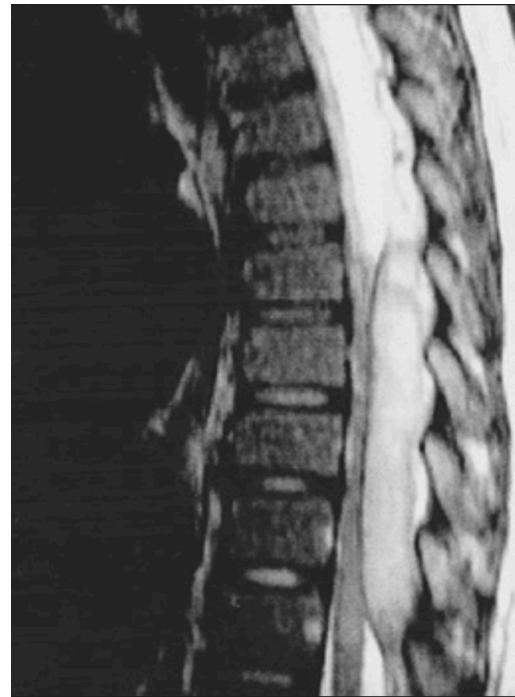

Cauda Equina SyndromeZ

- Etiology: Severe compression of nerve roots in the thecal sac of lumbar spine, most commonly due to acute lumbar disc herniation

- Urgent MRI to confirm cause

- Prompt surgical decompression

- Should be performed within 24 hours, absolutely within 48 hours